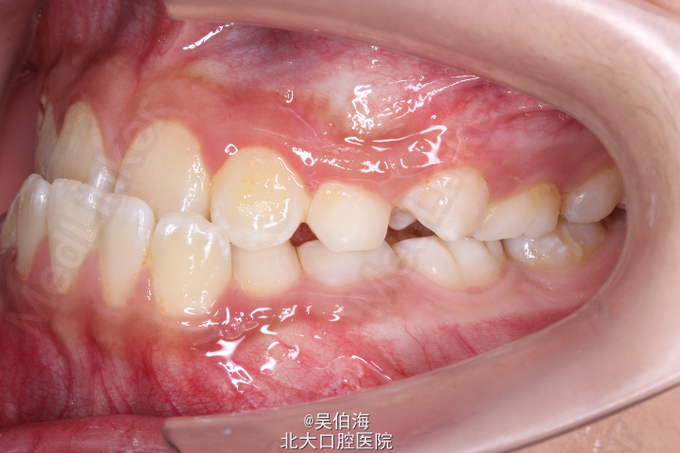

双侧三类磨牙关系,前牙反覆合反覆盖。能后退至切对切。有抿上唇的不良习惯。

安氏三类(假性) 第一期佩戴Frank三功能矫治器纠正前牙反合,择期行第二期固定矫治。